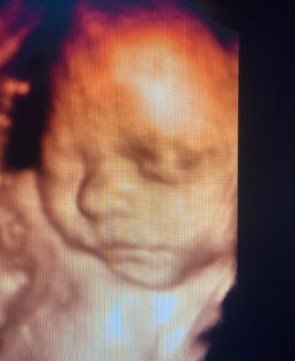

Tercer trimestre

En esta etapa continuamos con el control de la analítica y los tratamientos necesarios, que se realizan en todas las consultas, la identificación de la situación fetal, su crecimiento, la valoración de la placenta y del líquido amniótico. Así como el estudio de la circulación materno-fetal mediante el Doppler color de La arteria umbilical. A través de ecografías y estudios complementarios se comprueba el bienestar del bebé, su evolución final y cualquier cambio que pueda requerir una vigilancia más estrecha. Este control permite llegar al final del embarazo con la máxima seguridad tanto para la madre como para el bebé.

Cara